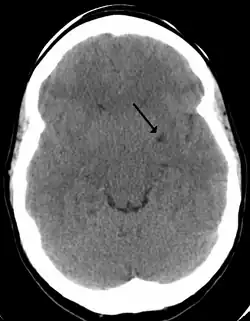

Perivascular spaces are most commonly located in the basal ganglia and white matter of the cerebrum, and along the optic tract.[13] The ideal method used to visualize perivascular spaces is T2-weighted MRI. The MR images of other neurological disorders can be similar to those of the dilated spaces. These disorders are:[7]

Perivascular spaces are distinguished on an MRI by several key features. The spaces appear as distinct round or oval entities with a signal intensity visually equivalent to that of cerebrospinal fluid in the subarachnoid space.[7][14][15] In addition, a perivascular space has no mass effect and is located along the blood vessel around which it forms.[14]

The clinical significance of perivascular spaces comes primarily from their tendency to dilate. The importance of dilation is hypothesized to be based on changes in shape rather than size.[13] Enlarged spaces have been observed most commonly in the basal ganglia, specifically on the lenticulostriate arteries. They have also been observed along the paramedial mesencephalothalamic artery and the substantia nigra in the mesencephalon, the brain region below the insula, the dentate nucleus in the cerebellum, and the corpus callosum, as well as the brain region directly above it, the cingulate gyrus.[5] Upon the clinical application of MRI, it was shown in several studies that perivascular space dilation and lacunar strokes are the most commonly observed histological correlates of signaling abnormalities.[13]